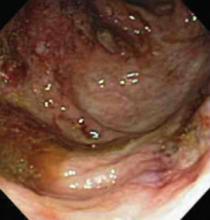

A healthy 17-year-old white patient with mild acne was treated with isotretinoin (Accutane), 40 mg/day. After a month of treatment, the acne got worse and the patient complained of polymyalgia and arthralgia.

An examination revealed numerous nodules and cysts covered by hemorrhagic crusts on his chest and back (FIGURE). The patient had severe muscular tenderness with gait disability. Leukocytosis and elevated erythrocyte sedimentation rate (ESR) were found; creatinine phosphokinase was within the normal values.

Diagnosis: Acne fulminans

Signs and symptoms. It is characterized by sudden onset ulcerative crusting cystic acne, mostly on the chest and back. Fever, malaise, nausea, arthralgia, myalgia, and weight loss are common.